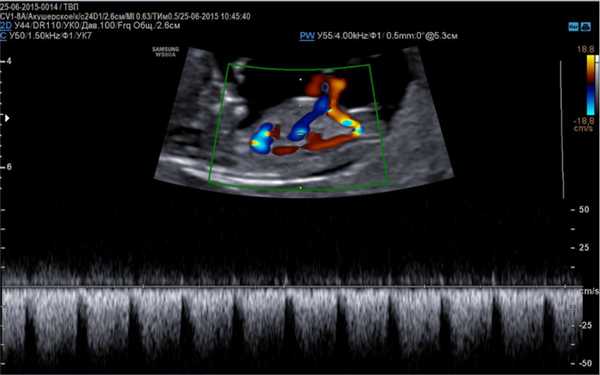

- УЗИ беременности. При стандартном сканировании в М-режиме удается одновременно зарегистрировать частоту и ритм сокращений предсердий и желудочков, оценить атриовентрикулярное проведение импульса. Методика дополняется импульсно-волновой допплерографией камер сердца, легочных сосудов, сосудов пуповины.

- Допплерэхокардиография - используется для изучения гемодинамики в сосудах и камерах сердца, а также оценки сердечного ритма. Проводится в режиме ЦДК и импульсной допплерографии.